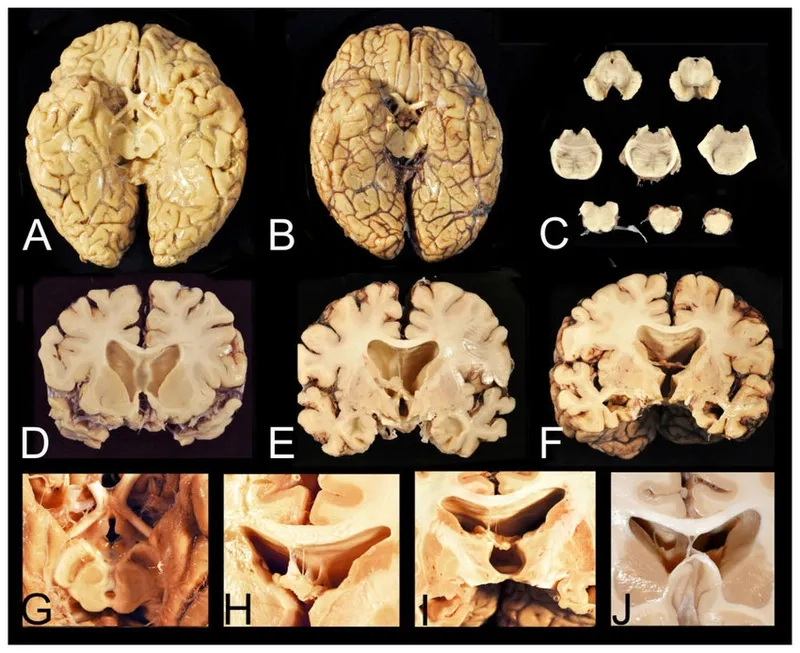

- The accumulation of an abnormal protein called tau forms clumps that slowly spread throughout the brain, killing brain cells and leading to progressive decline.

- As the disease progresses, cognitive impairment becomes more pronounced, with individuals experiencing significant memory loss, confusion, and impaired judgment, which can resemble Alzheimer's disease.

- In later stages, motor symptoms may develop, including tremors, slowed movement (parkinsonism), and difficulty with speech and swallowing, reflecting widespread brain damage.

Visualizing concepts related to CTE